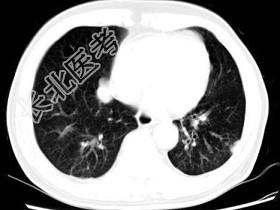

- 单项选择题男,64岁, 咳嗽半月,咯血1天, 不发热,结合图像, 最可能的诊断是 ( )

A、金葡菌肺炎

B、肺转移瘤

C、肺结核

D、结节病

E、组织胞浆菌病